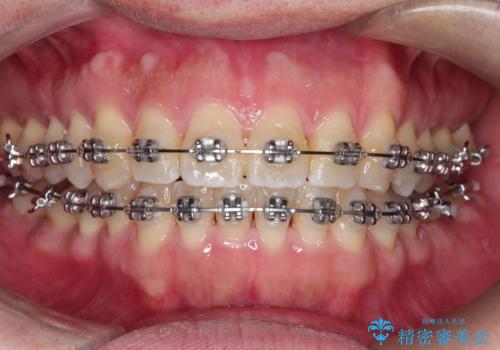

ワイヤーによる全体的ながたつきの矯正治療

- 30代男性

- メタル

- 1年3ヶ月

- 全体的ながたつきを治したいとのことで来院されました。

ワイヤー矯正とマウスピース矯正の二つの器具での治療をご案内し、ワイヤー矯正を選択されました。

インビザラインを装着するのがめんどうなので、ワイヤーの方があっているとのことで今回の治療方法を選択されました。